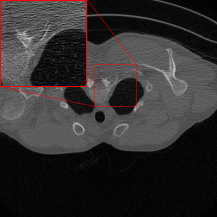

Figure 3 shows reconstruction results from the three networks for a test sample from the LoDoPaB-CT test dataset and one from the 2016LDCTGC dataset. All trained networks successfully improve the FBP reconstructions, as shown by the improved image quality and finer structural details.

Figure 3: Reconstruction results for two test samples from the LoDoPaB-CT test dataset (top row) and the 2016LDCTGC dataset (bottom row). The first column displays the ground truth, followed by the FBP in the second column. The next three columns present reconstructions by the Gaussian denoisers DRUNet, KBNet, and Restormer. Each pretrained denoiser model was trained for 96 epochs on 1791 image pairs from either the LoDoPaB-CT training dataset or the 2016LDCTGC dataset. The proposed two-stage method effectively enhances the FBP reconstructions in each case, as demonstrated by the PSNR and SSIM metrics provided below each subimage.